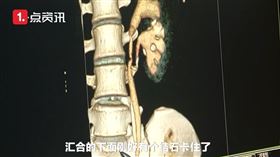

男尿尿咖啡色又卡1.8公分結石 險敗血症

尿色像咖啡可不是小事!70歲陳姓男子為中部知名塑膠射...